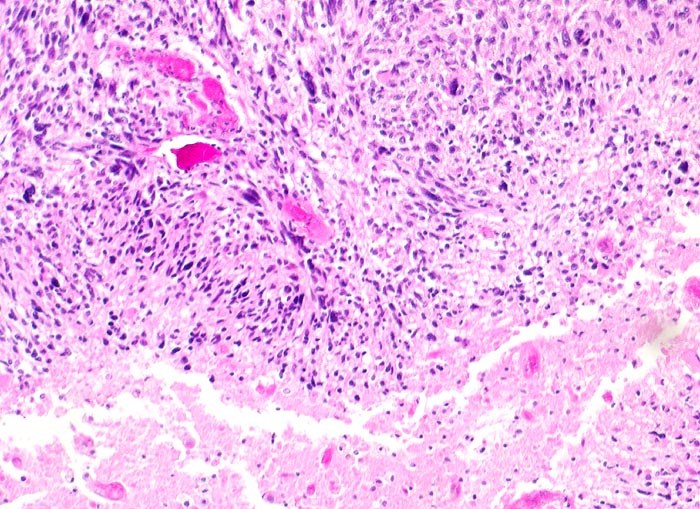

PathoPic ID 5199 - Glioblastoma multiforme (WHO IV)

Glioblastoma multiforme (WHO IV)

maligner Tumor

Hirn temporal

Nervensystem

Parallele Ausrichtung der Tumorzellen (

Palisadierung) angrenzend an die

Tumornekrose

Seit zwei Monaten zunehmende Persönlichkeitsveränderungen, Kopfschmerzen und progrediente fokal neurologische Zeichen.

Histologie

100

52